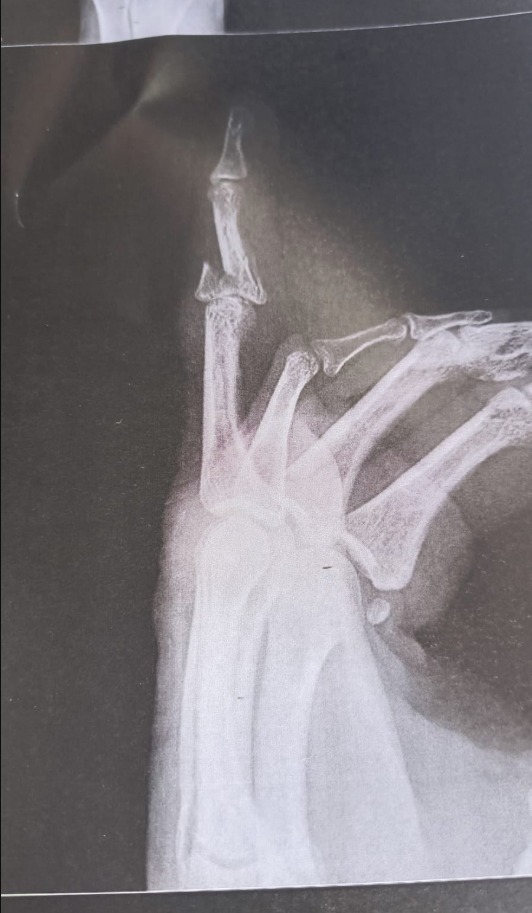

Raio-X mostra a fratura em um dos dedos da vítima

Durante o desentendimento, o suspeito utilizou um copo térmico de metal, do tipo Stainless, para agredir a garçonete. O golpe atingiu a mão da vítima e provocou a fratura de um dos dedos. De acordo com o laudo pericial anexado ao inquérito, a lesão afastou Helena do trabalho por mais de 30 dias, o que caracteriza lesão corporal de natureza grave, conforme previsto no artigo 129 do Código Penal.